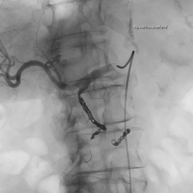

Patienten die sich einer regelmäßigen Blutwäsche unterziehen müssen (Dialyse), haben dafür einen operativ geschaffenen Gefäßzugang zum Punktieren (Dialysefistel/Dialyseshunt). Dazu wird eine Hautvene direkt an eine Arterie angeschlossen. In dieser Shuntvene können Einengungen und Verschlüsse auftreten, die mit vielen interventionellen Methoden behandelbar sind. Diese Behandlungen führen wir über einen Zugang in der Shuntvene meist ambulant in Zusammenarbeit mit der jeweiligen Dialyseeinrichtung durch.